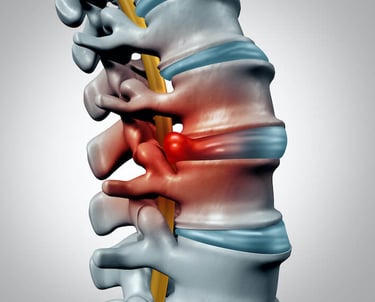

What is a Herniated Disc?

A herniated disc occurs when one of the discs in your spine slips out of place or ruptures, pressing on nearby nerves. This can lead to sharp pain, numbness, or tingling, especially in the back, neck, arms, or legs. Whether from an injury, poor posture, or age-related wear and tear, this common issue can drastically affect your quality of life.